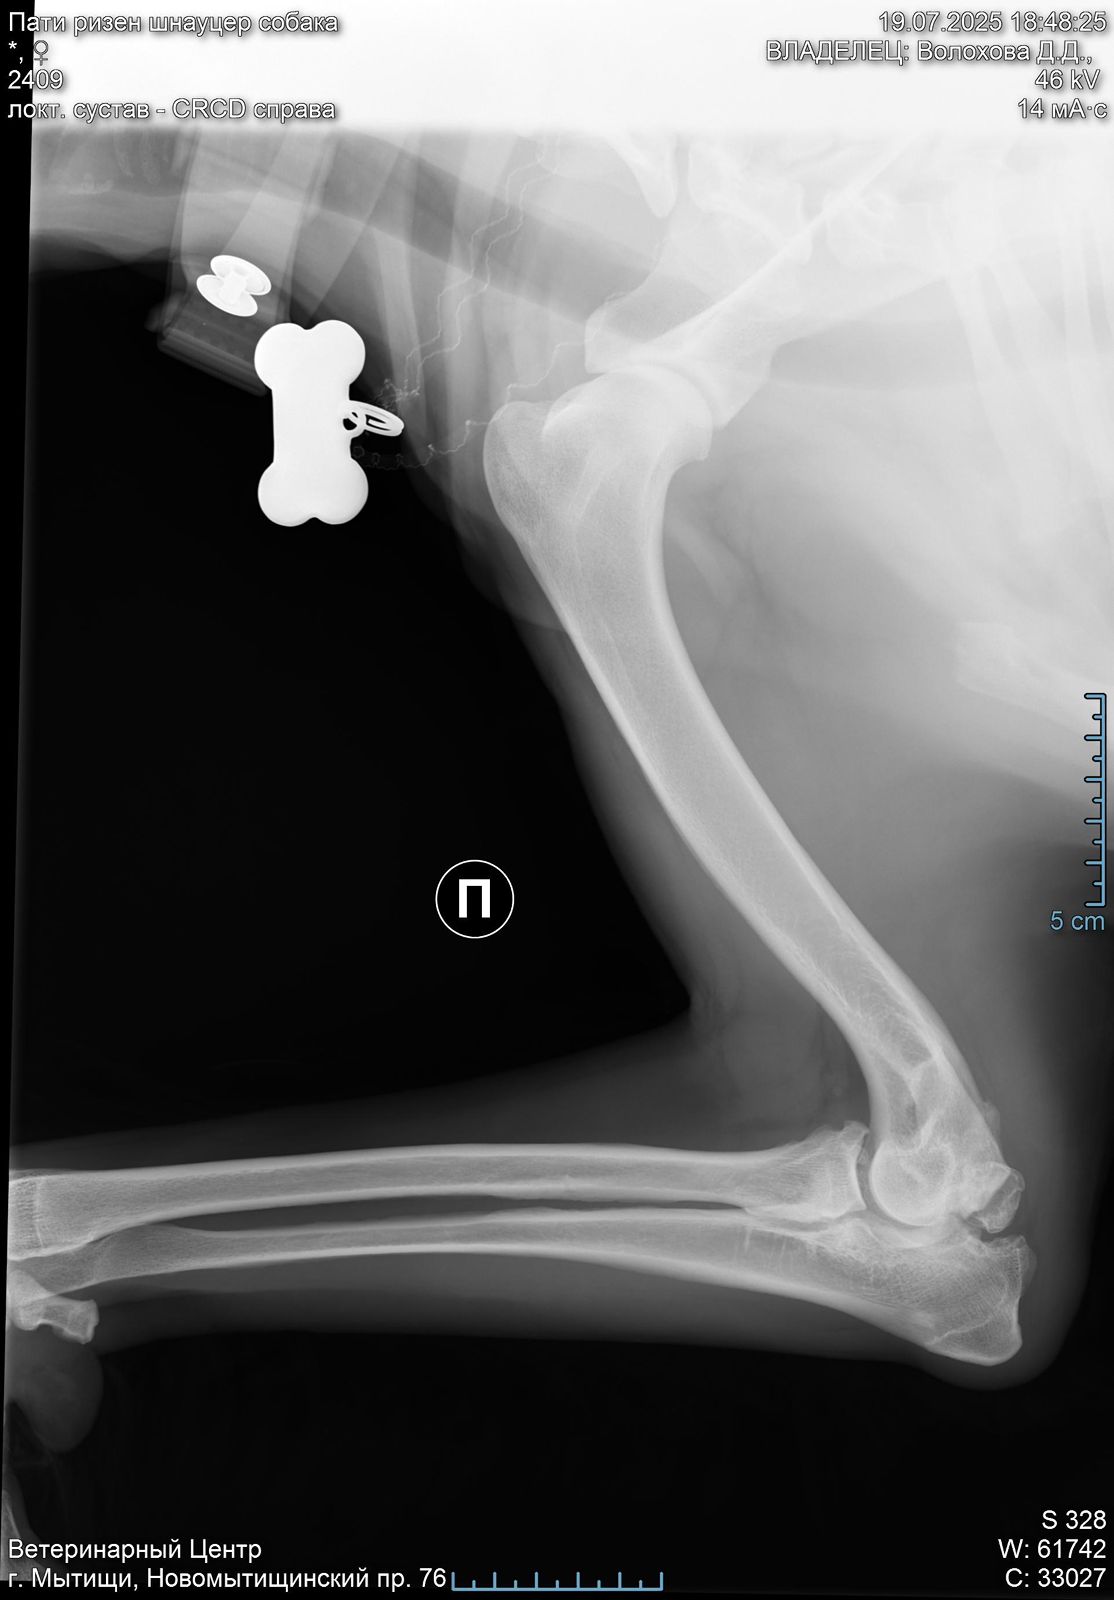

Лапа

В правом локтевом суставе у Пати болтается 2 осколка кости( от мыщелков).

Их надо убирать.

Проблема не приобретенная у нас, а врожденная или травма в прошлой жизни.

Операция сложная, и делается 2 способами: на открытом суставе или через артроскоп ( если осколки меньше 1 см).

Поэтому вначале требуется КТ, чтоб понимать, какой метод в нашем случае актуален.

Есть шансы поиметь осложнения при обоих. У каждого есть плюсы и минусы.

Но пока есть шанс убрать осколки и жить вполне обычной жизнью ( не спортивной, но и не инвалид).

Артроз сустава никуда не исчезнет, но если повезет, и сильно прогрессировать не будет.

При таком поражении сустава удивительно, что нет выраженной хромоты.

Левый локтевой пока под вопросом, есть там проблемы или нет. КТ покажет.